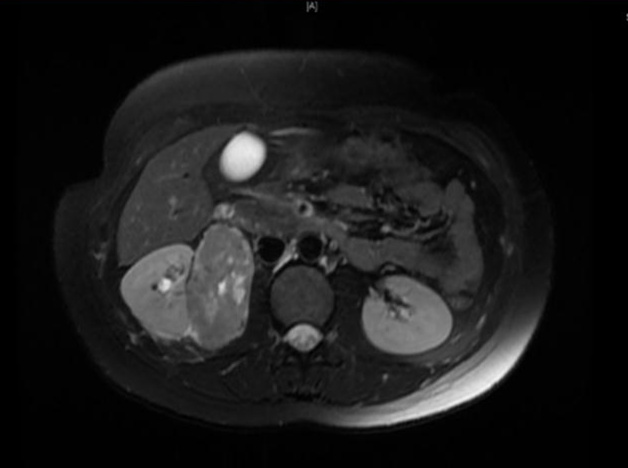

泌尿外科成功为一妊娠18周孕妇腹腔镜下切除肾脏巨大肿物

一旦肾脏长了一个肿物该怎么治疗,答案可能很简单——手术。但是对于一位多次怀孕不成功的孕妇,这个问题可能就没那么容易了。 不久前,一位挺着大肚子的特殊患者慕名来到了北医三院泌尿外科主任马潞林教授的门诊。患...